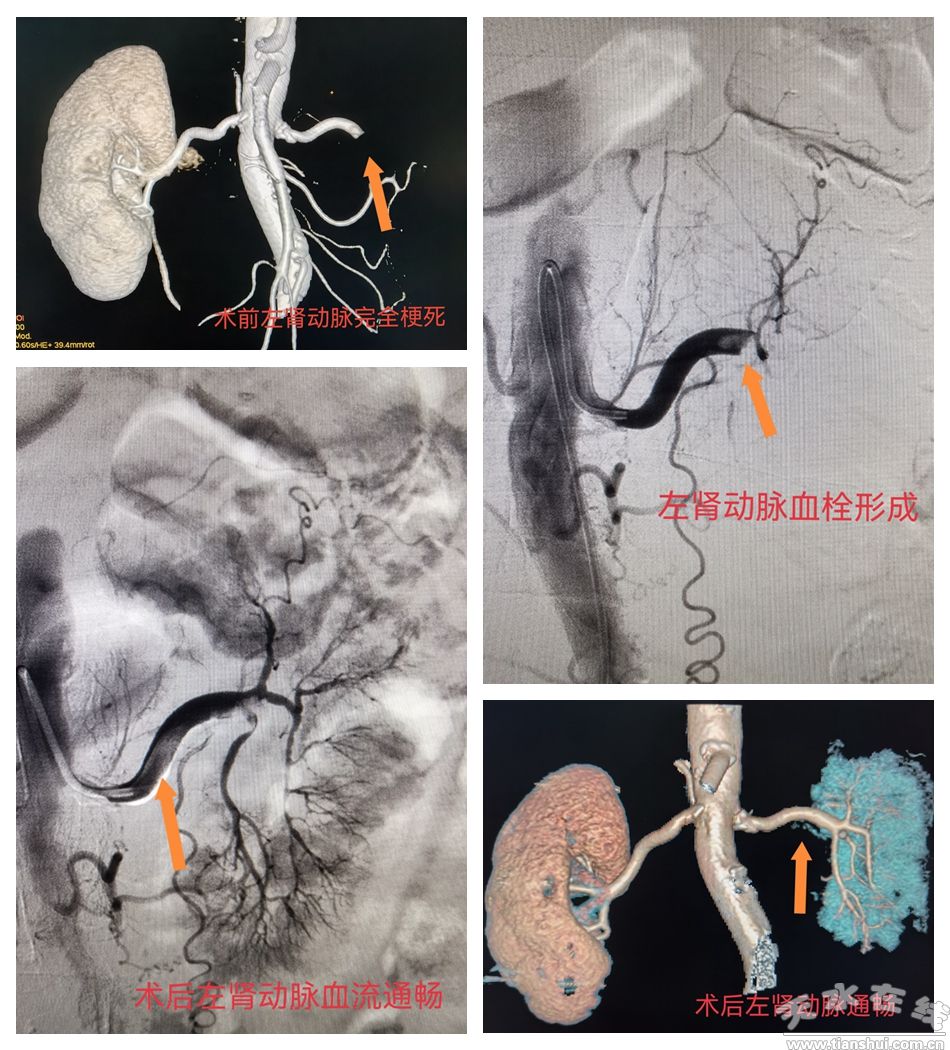

患者為老年女性,因“突發(fā)左側腰腹部劇痛1天余”緊急前往我院急診科就診。接診醫(yī)生高度警惕,立即啟動“綠色通道”為患者安排腹部增強CT檢查,提示左腎動脈完全閉塞、腔內大量血栓,且肌酸激酶、D-二聚體及腎功能指標均明顯異常,已出現(xiàn)腎臟缺血壞死征象。急性腎動脈栓塞發(fā)病急、進展快,延誤治療易導致腎功能衰竭,患者情況十分危急。

急診科第一時間啟動緊急預案,組織多學科(MDT)專家會診,最終確定采用介入微創(chuàng)治療方案——腎動脈取栓術+置管溶栓術,以快速恢復腎臟血供。手術全程歷時1.5小時,在局部麻醉下順利完成。醫(yī)生通過微創(chuàng)穿刺建立通路,將導管精準送達閉塞部位,成功清除血栓并留置溶栓導管持續(xù)治療。整個手術過程安全高效、創(chuàng)傷小,有效避免了傳統(tǒng)開放手術的大創(chuàng)傷及腎切除風險。

術后,患者被轉入介入醫(yī)學科住院觀察治療。術后第3天復查顯示,腎動脈血流通暢,腎功能逐步改善,腰腹部劇痛癥狀快速緩解;住院第7天,患者各項指標趨于穩(wěn)定,達到出院標準順利出院,恢復情況良好。